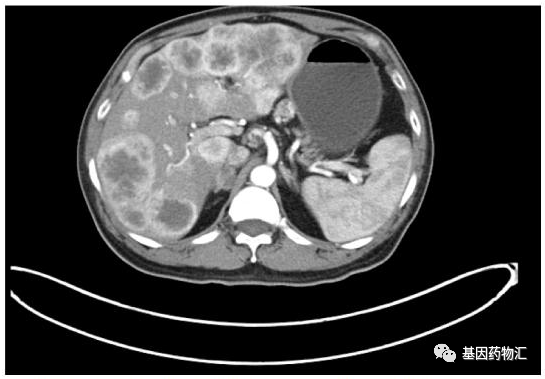

ROS1:曲替尼成为ROS1一二线脑转移优先推荐,效抗脑转2019年8月,FDA加速批准了全球第三款广谱“治愈系”抗癌药Entrectinib(Rozlytrek,恩曲替尼,RXDX-101)上市,用于治疗成人和儿童患者神经营养原肌球蛋白受体激酶(NTRK)融合阳性、初始治疗后局部晚期或转移性实体肿瘤进展或无标准治疗方案的实体瘤患者,以及ROS1阳性非小细胞肺癌(NSCLC)患者。PD-1高表达晚期NSCLC,药成为一线优先推荐,+Y双免推荐级别升至1级对于PD-L1高表达的晚期非小细胞肺癌患者,无论是鳞

第四代EGFR抑制剂来了!奥希替尼耐药不用怕,六大处理方案全梳理!

一肺腺癌女性62岁患者,先后进行了化疗、吉非替尼、厄洛替尼耐药后,出现T790M突变用奥希替尼治疗。SYMPHONY研究是BLU-945的首次人体1/2期开放性标签临床试验,旨在评估BLU-945单药和联合奥希替尼治疗对EGFR-TKI耐药的晚期NSCLC患者的安全性、耐受性和有效性。四、新靶点药或“四代”TKI1.U3-14022020WCLC报告了一项I期临床研究,评估晚期EGFR突变NSCLC患者在EGFR-TKIs奥希替尼治疗和铂类化疗失败后使用HER3抑制剂U3-1402(patritumab-

一至四代EGFR靶向药物大汇总

图五吉非替尼、奥希替尼、BLU-701、BLU-945对不同EGFR突变的IC50,绿色为强抑制,黄色中等抑制,紫色为弱或无抑制2022年的AACR大会报道了BLU-945的I期临床研究,剂量递增阶段33例患者的数据,这些患者先前接受过超过1种EGFR靶向药治疗,97%接受过奥希替尼治疗,64%有脑转移,55%为亚裔。一项来自中国的很小型的回顾性研究,纳入6例基线无症状脑转移EGFR突变患者,全部为非鳞癌,接受30mg达可替尼治疗,在5例疗效可评估患者中,2例脑转移完全缓解,3例脑转移稳定,颅内客观缓解率